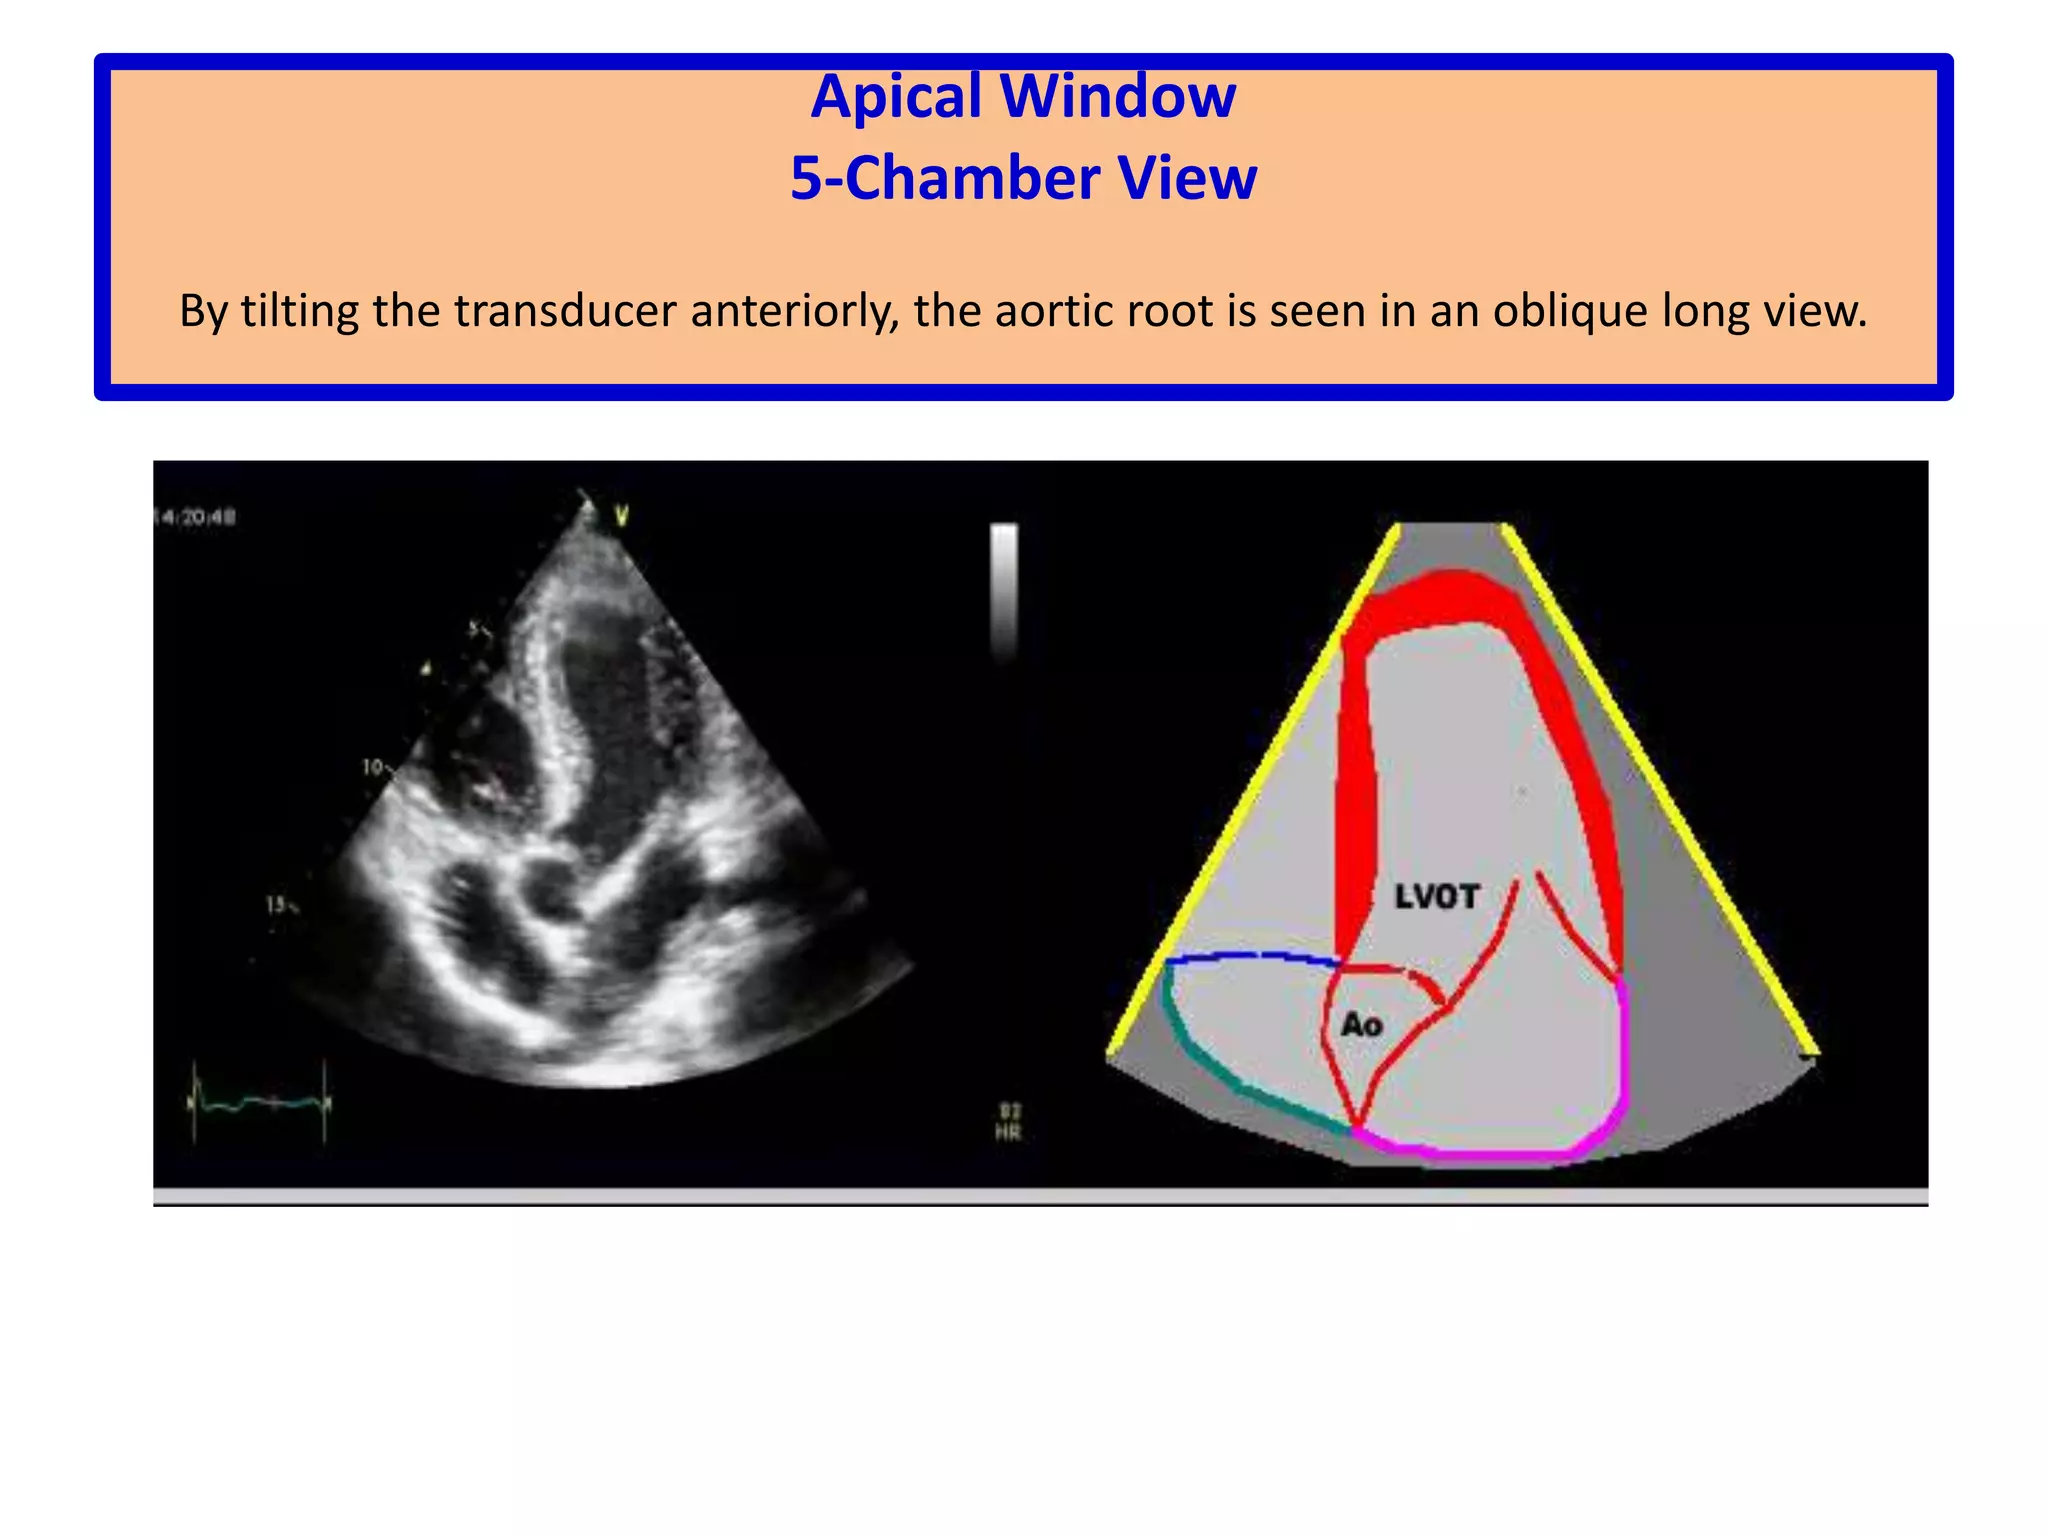

Apical Window5-Chamber ViewBy tilting the transducer anteriorly, the aortic root is seen in an oblique long view.

Apical Window5-Chamber ViewBytilting the transducer anteriorly, the aortic root is seen in an oblique long view.